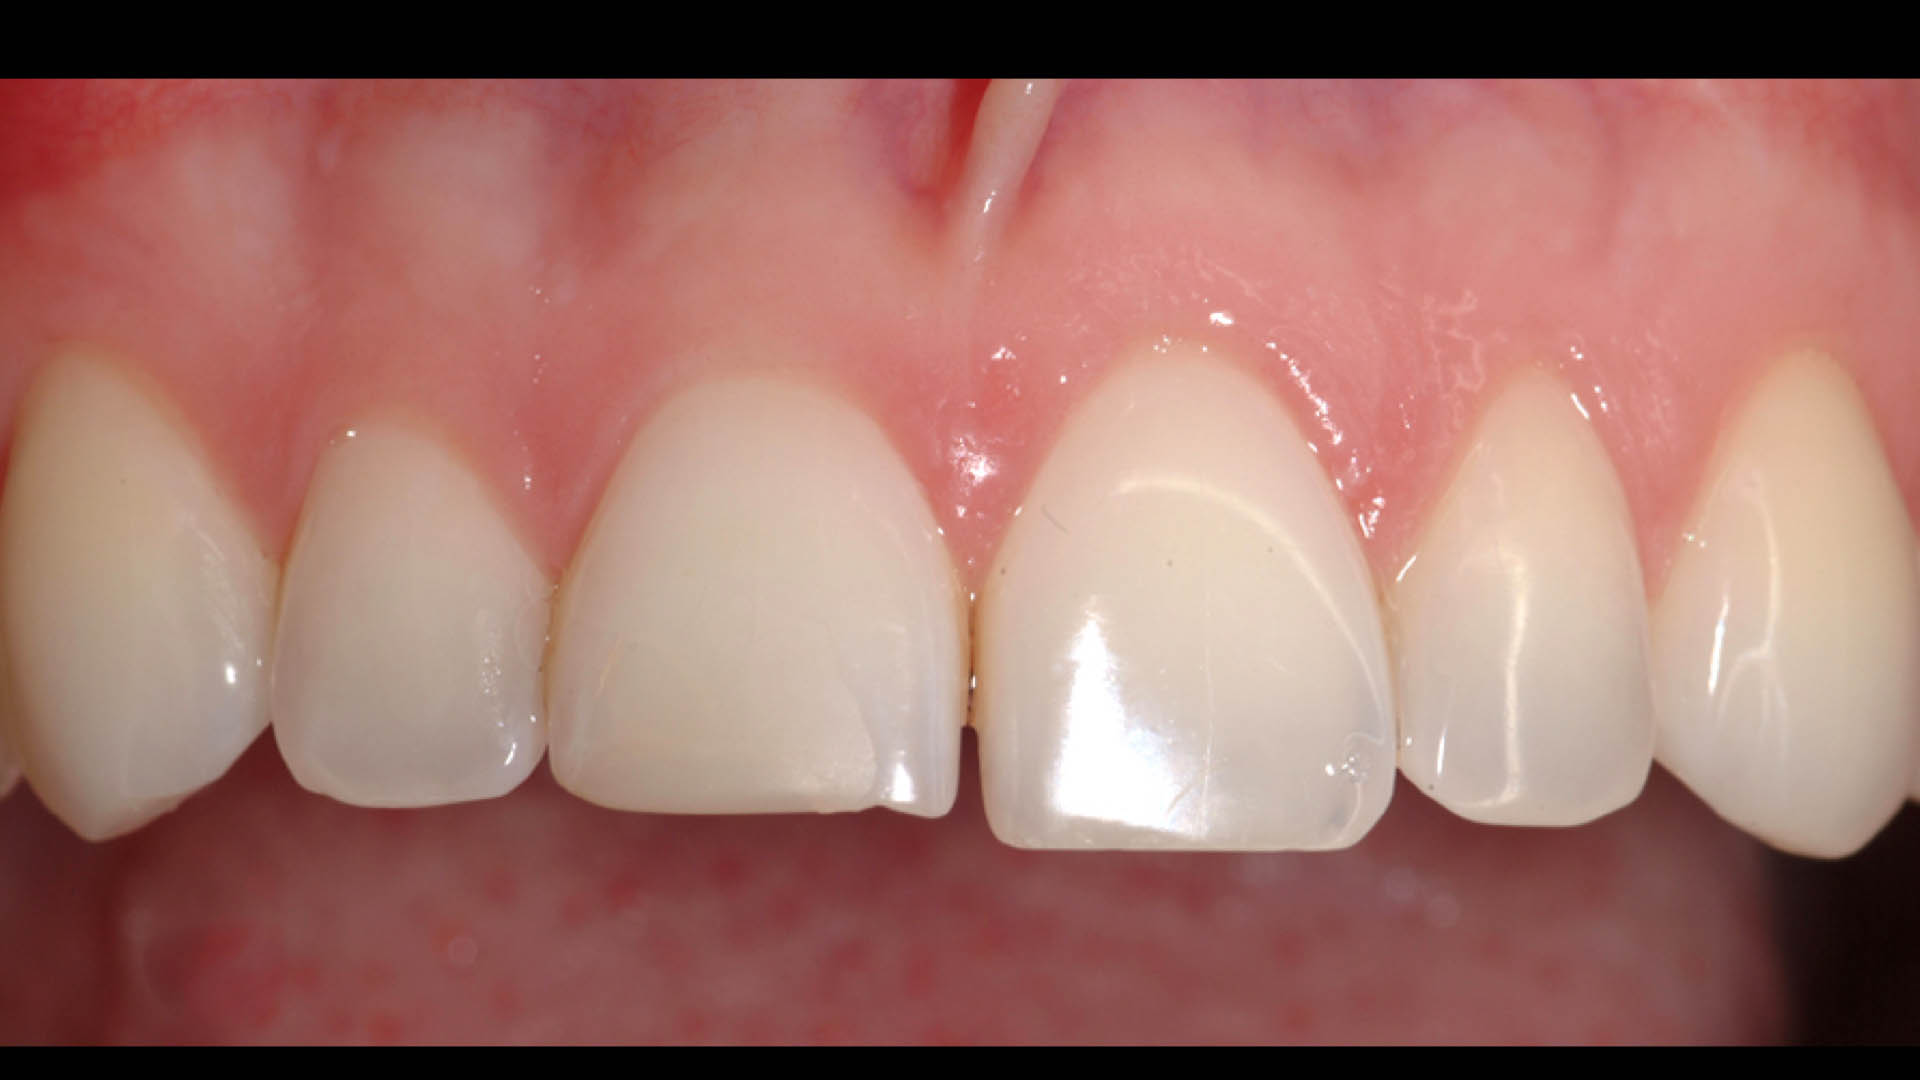

Take a glimpse into the magic of Coral Gables Dentistry through our before and after pictures. See firsthand the incredible smile makeover transformations that have brought confidence and joy to our patients.